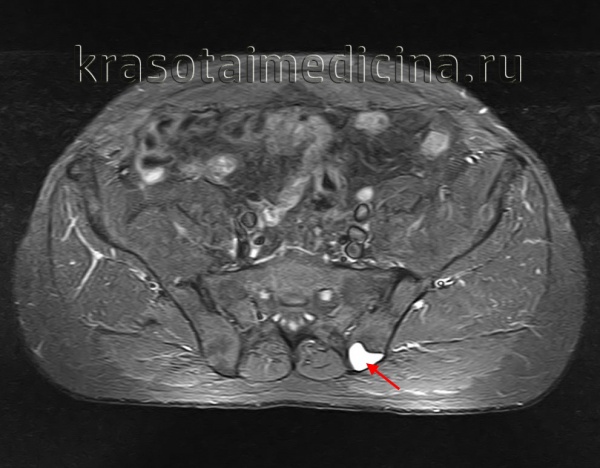

Кисты и некрозы костей можно диагностировать с помощью следующих методов:

- Осмотр врача (сбор жалоб, пальпация больного места) пораженной кости в нескольких проекциях или магнитно-резонансная томография (МРТ)

Для диагностики аневризматических костных кист запястья врачи обычно проводят рентгенологическое исследование Рентгенологическое исследование Зачастую врач может диагностировать костно-мышечное заболевание на основании анамнеза и по результатам физикального осмотра. Чтобы облегчить постановку или подтверждение диагноза, иногда необходимы. Прочитайте дополнительные сведенияХирургическое удаление всей кисты является наиболее результативным видом лечения, но иногда наблюдается ее рецидив, особенно при неполном удалении кисты. Лучевой терапии следует по возможности избегать, поскольку в дальнейшем возможно развитие злокачественных опухолей. Однако лучевая терапия Лучевая терапия для лечения онкологического заболевания Радиация является формой интенсивной энергии, генерируемой радиоактивным веществом, таким как кобальт, или специализированным оборудованием, например (линейным) ускорителем атомных частиц. Облучение. Прочитайте дополнительные сведения может быть показана для лечения кист позвоночника, не подлежащих хирургическому лечению и сдавливающих спинной мозг.

Для диагностики однокамерных костных кист врачи обычно проводят рентгенологическое исследование Рентгенологическое исследование Зачастую врач может диагностировать костно-мышечное заболевание на основании анамнеза и по результатам физикального осмотра. Чтобы облегчить постановку или подтверждение диагноза, иногда необходимы. Прочитайте дополнительные сведения (МРТ) или в некоторых случаях компьютерная томография Компьютерная томография (КТ) и магнитно-резонансная томография (МРТ) Зачастую врач может диагностировать костно-мышечное заболевание на основании анамнеза и по результатам физикального осмотра. Чтобы облегчить постановку или подтверждение диагноза, иногда необходимы. Прочитайте дополнительные сведенияЧаще всего такие кисты лечат путем инъекций кортикостероидов (часто многократных), обработанной костной пастой или синтетическими заменителями костной ткани. Иногда проводят хирургическое лечение для извлечения содержимого кисты из кости, соскабливая кисту с помощью специального инструмента в виде лопатки (кюретаж), а также выполняют трансплантацию кости из одного участка в другой (пересадка кости). Опухоли обычно развиваются у подростков и лиц в возрасте 20–30 лет, но могут возникать в любом возрасте.